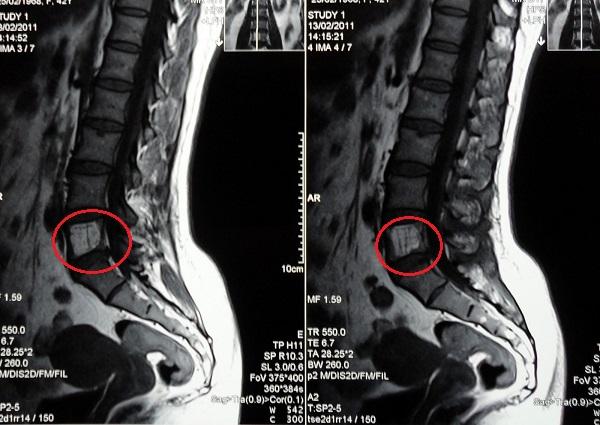

Диагностика заболевания

На начальных этапах заболевания симптомы могут быть слабо выражены, поэтому его, как правило, выявляют случайно во время обследования по другим причинам, связанным с опорно-двигательным аппаратом.

Если у человека появляются боли в спине, которые ранее не беспокоили, ему настоятельно рекомендуется незамедлительно обратиться к неврологу, ортопеду или хирургу для проведения обследования.

Диагностика осуществляется под наблюдением специалистов с использованием компьютерной томографии, магнитно-резонансной томографии и рентгенографии. В случае подозрения на гемангиому позвоночника, лечащий врач, совместно с вертебрологом и нейрохирургом, принимает решение о необходимости хирургического вмешательства.